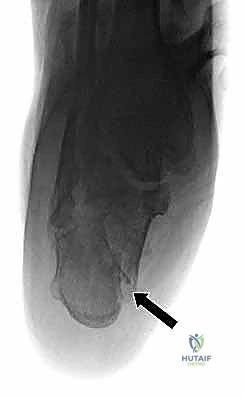

- التصوير بالأشعة السينية (X-rays): لأخذ فكرة أولية عن الكسر (زوايا بوهلر وجيسان - Bohler’s and Gissane’s angles).

- الأشعة المقطعية (CT Scan): وهي الخطوة الأهم والأكثر حيوية. توفر الأشعة المقطعية صوراً ثلاثية الأبعاد وتقاطعاً دقيقاً للكسر، مما يسمح بتصنيف الكسر (نظام ساندرز - Sanders Classification) وتحديد عدد الشظايا العظمية ومدى انزياحها داخل المفصل. بناءً على هذه الأشعة، يضع الدكتور هطيف خطته الجراحية الدقيقة.

5. التثبيت النهائي باستخدام الشرائح والمسامير (Plating)

يتم وضع شريحة تيتانيوم (Titanium Plate) مصممة خصيصاً لتطابق الشكل التشريحي لعظم الكعب. يتم تثبيت هذه الشريحة بمسامير قوية لتوفير ثبات ميكانيكي صلب يسمح بالالتئام السليم ويمنع انهيار العظم مرة أخرى. في بعض الحالات التي يوجد فيها فراغ عظمي كبير، قد يستخدم الدكتور هطيف طعوماً عظمية (Bone Grafts) لملء الفراغ.